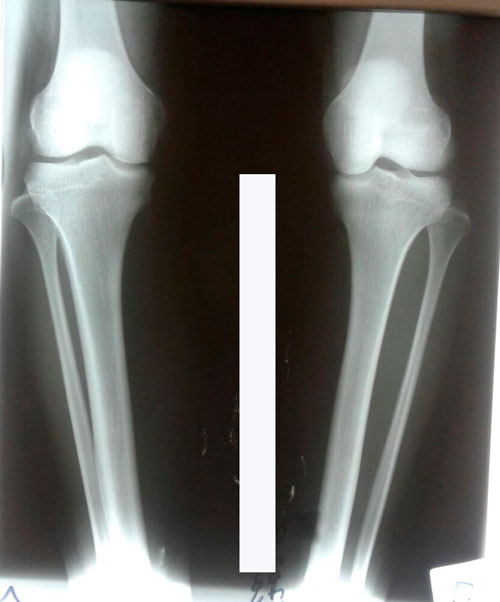

Исходник - 24 года.

2-я ротация.

Дата операции 19.07.2017г.

Дата операции 19.07.2017г

Дата снятия аппаратов 17.10.2017г.

Срок лечения 88 дней.